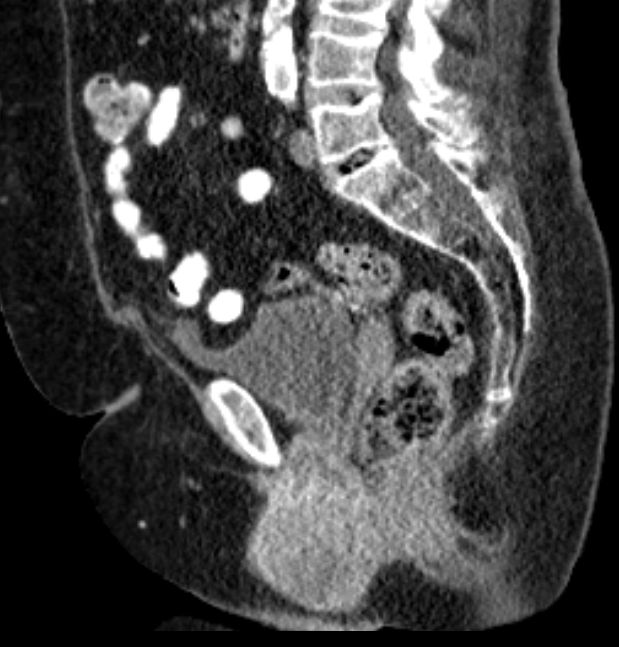

82-jährige Frau mit einem Leiomyosarkom der Vulva rechts pT2a N0 M0, V1, G2.

Klinik: Vulva-Tumor rechts. Der Tumor ist relativ glatt begrenzt und gut 5 cm groß; er ist auf dem absteigenden Schambeinast beweglich und reicht dicht bis an die Urethralöffnung heran.

Makroskopie: subepidermal gelegenes Leiomyosarkom. Zentral gelegen ein die Haut vorwölbender, 6,5 cm messender Tumor.

Mikroskopie: Subepithelial in Zügen und Bündeln angeordnete, teils epitheloide und teils spindlige Tumorzellen. Oftmals längsovale Zellkerne mit abgestumpften Kernenden. Daneben Areale mit erheblicher Zell- und Kernpolymorphie. Ausbildung bizarrer Riesenkerne. Schmaler Zytoplasmasaum. Herdförmige Tumornekrosen mit vitalen, um Blutgefäße angeordneten Tumorzellen und weiter entfernt gelegenen nekrotischen Arealen. Ausbildung von Tumorriesenzellen. Oftmals Apoptosen. Einzelne Tumoreinbrüche in Blutgefäße.

8 Monate nach Primärtherapie auftreten von Knochenmetastasen. Kein lokales Rezidiv.